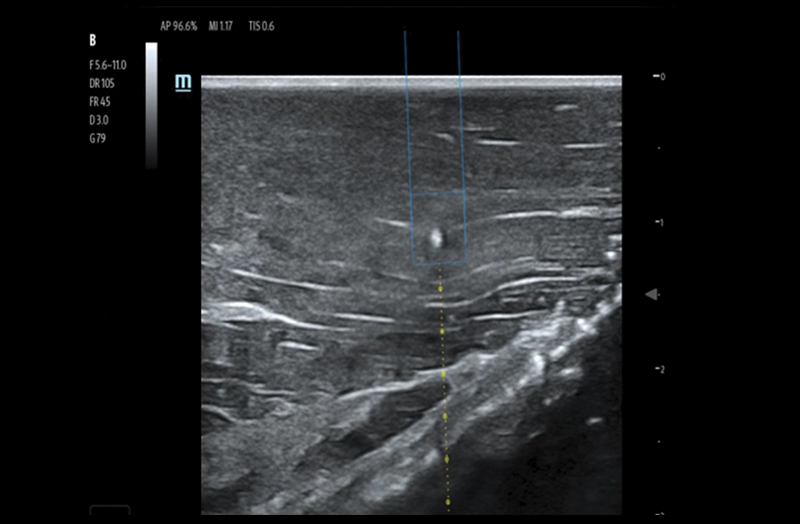

Needle Guidance